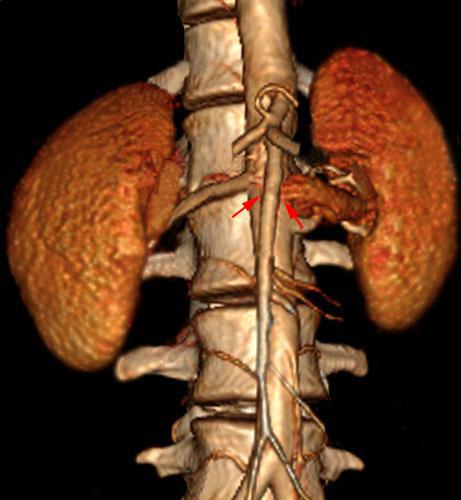

Síndrome del cascanueces retroaórtico